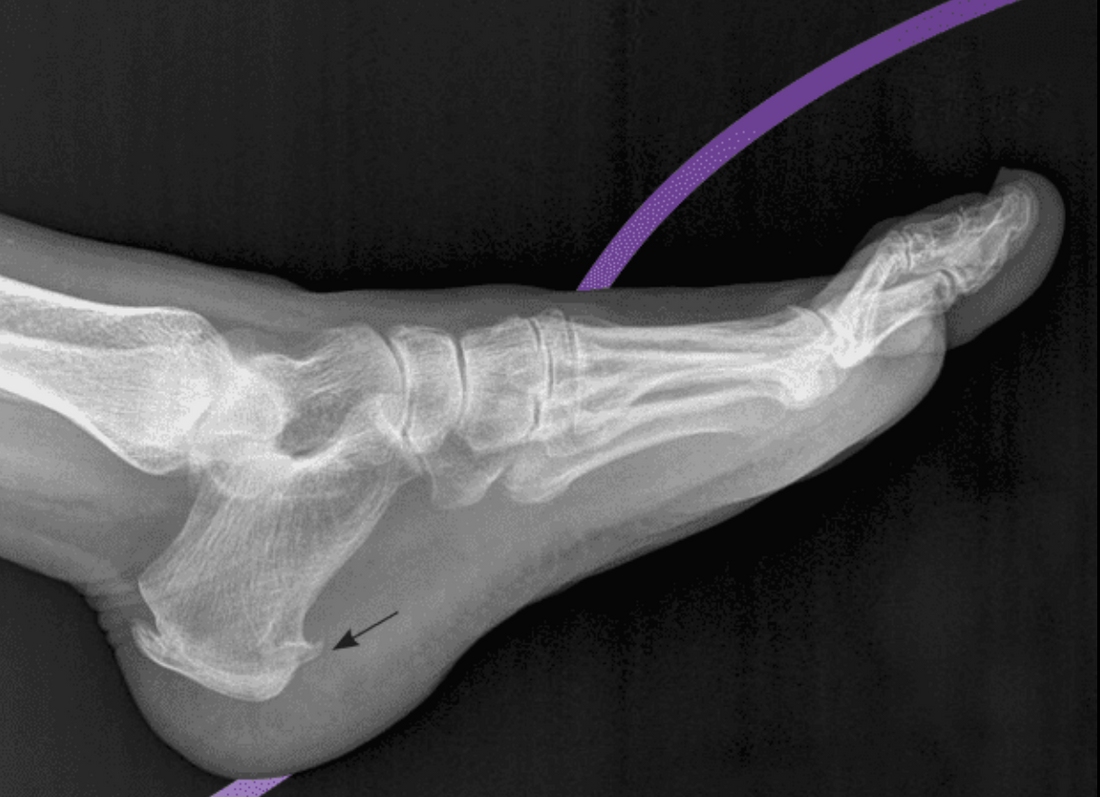

Understanding Heel Spurs: Symptoms and Causes

A calcaneal spur, commonly known as a heel spur, is a bony outgrowth that develops on the underside of the heel bone. This condition is often associated with plantar fasciitis, an inflammation of the plantar fascia—a band of tissue that supports the arch of the foot. Heel spurs can cause considerable discomfort, especially during weight-bearing activities like standing or walking.